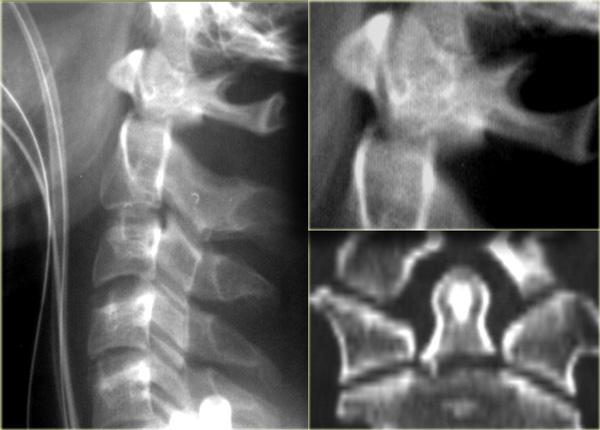

Bên trái là hình ảnh của một nam giới 20 tuổi bị tai nạn xe cơ giới lật xe.

Trước tiên hãy quan sát các hình ảnh bên trái.

Sau đó tiếp tục đọc.

Các dấu hiệu trên X-quang bao gồm:

- Tăng gấp tại mức C4-C5 với khoang gian gai rộng ra

- Trật khớp tại mức C4-C5 với khoảng trượt khoảng 25% (tức là di lệch ra trước 25% đường kính trước-sau của thân đốt sống)

- Mất thẳng hàng của các mỏm gai trên phim thẳng (AP), chỉ có thể xảy ra do chấn thương xoay. Mỏm gai bị tổn thương hướng về phía bên bị tổn thương

- Do xoay, các mỏm gai của C4 và C5 trông ngắn hơn trên phim nghiêng

CT xác nhận trật khớp một bên.

Khớp mặt bên đối diện chỉ bị giãn cách.